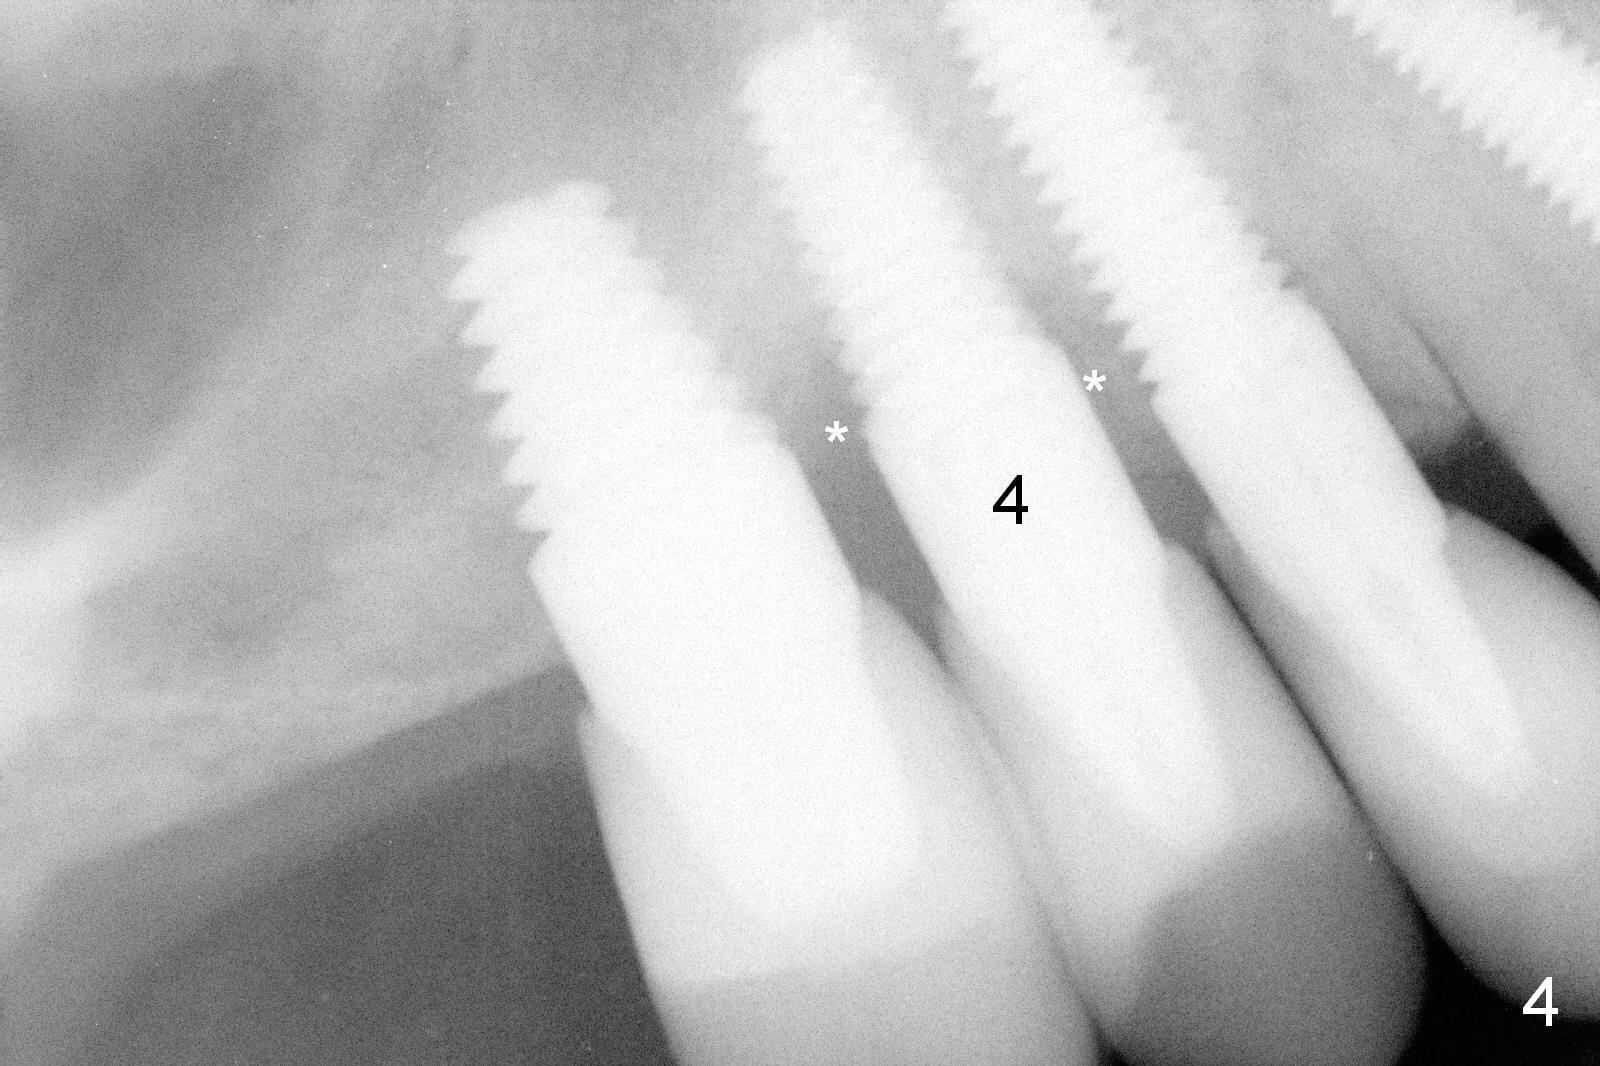

There is mild bone loss around the implant at #4 22 months post cementation (Fig.3).  Two months later, the patient complains of bleeding.  Exam reveals deep pocket between #3 and 4 (palatal) with bleeding on probing.